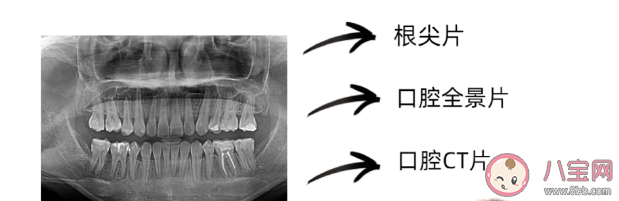

口腔科中的拍片类型包括哪些

1、小牙片

小牙片是常用的辅助检查手段,能拍摄单颗牙齿,了解根尖病变情况,评估牙齿龋坏程度。

2、全景片

全景片能观察口腔中每个牙齿的形态、牙齿所处位置、周围颌骨情况。通过该检查能了解牙齿中有没有阻生埋伏牙和多生牙,牙槽骨是否被吸收。

3、牙科CT

牙科CT能从三维角度下立体显示牙齿和颌骨情况。与前两者相比,CT检查清晰又全面,能准确了解外伤牙牙根折裂情况,了解囊肿大小,准确判断埋伏牙或多生牙所处位置,让手术更加安全且精准。